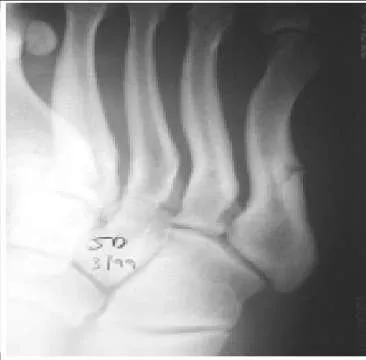

A patient sustained a fracture of the calcaneus 9 months ago. The fracture was treated with non-weight bearing and cast immobilization. The patient experiences constant pain and is unable to work. On examination, he has limited inversion, eversion motion of the foot, and lateral foot pain. Radiographs are presented. The recommended treatment is:

Correct Answer: Subtalar arthrodesis

In the presence of stiffness of the subtalar joint, physical therapy modalities are unlikely to improve the foot function. For the young active worker, an early subtalar arthrodesis is the most reliable procedure to return him to work and an active lifestyle. A triple arthrodesis is contraindicated in the absence of painful transverse tarsal arthritis.